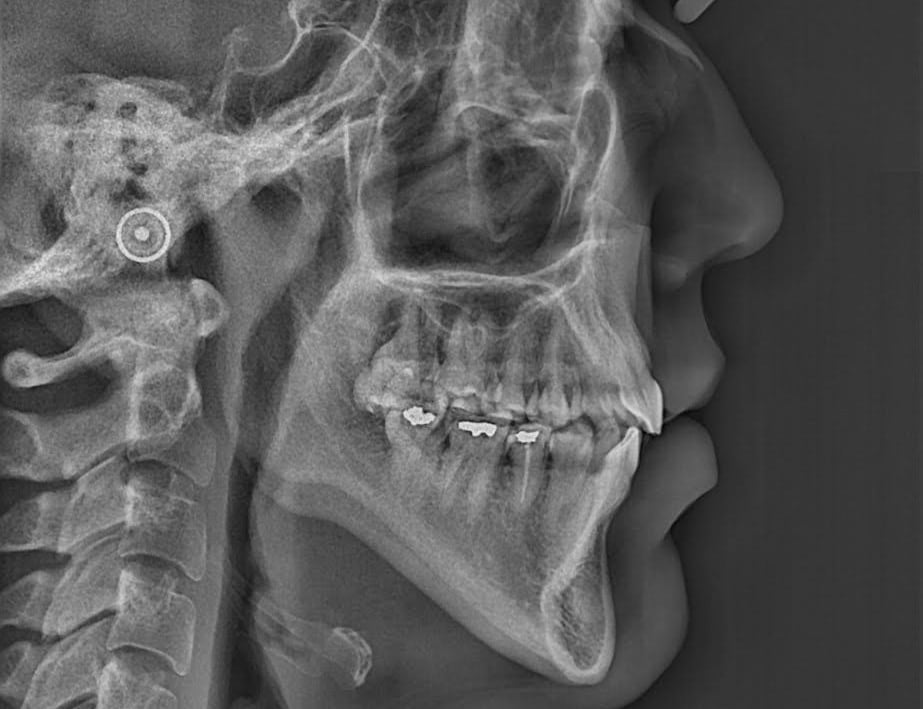

Durante las radiografías, se obtienen imagenes de los dientes y los huesos mediante rayos X.

Con motivo de una revisión dental, se toman radiografías interproximales (de aleta de mordida) según sea necesario. Se toman 1 o 2 de cada lado de la boca. Si tiene caries muy activas , puede que sean necesarias radiografías interproximales con mayor frecuencia. Estas radiografías se toman para detectar caries en los espacios interdentales y para comprobar el nivel óseo.

En las radiografías interproximales se puede observar el inicio de las caries antes de que sean visibles en la boca. Por lo tanto, es posible iniciar un tratamiento preventivo antes de realizar un empaste. Las radiografías interproximales también permiten evaluar el nivel óseo alrededor de los dientes y, por consiguiente, indicar si existe periodontitis.

En otros casos, puede ser necesario tomar una radiografía que abarque todo el diente. Estas radiografías se pueden utilizar, por ejemplo, para detectar caries o inflamación en el ápice de la raíz. Se toman, por ejemplo, antes de colocar una corona o en relación con un tratamiento de conducto.